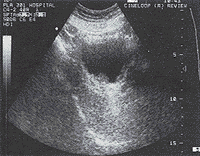

例2 男,71岁,间歇性无痛性血尿17年。既往多次和本次膀胱镜检及活检,均诊断为膀胱淀粉样变。超声检查:膀胱后壁偏右侧结节样隆起,大小约2.0cm×1.4cm,基底宽,中等均匀回声(图1)。CDFI:病灶内未见血流信号。另于左侧壁可见弥漫性隆起,最厚约0.5cm,中等均匀回声。膀胱镜检查:膀胱三角区右边块状肿物,表面不平呈菜花状。左侧壁及顶部散在病变。

图1 膀胱弥漫性分布结节样隆起病变

讨论:原发性膀胱淀粉样变为临床少见非肿瘤性疾病,其声像图酷似膀胱肿瘤极易误诊〔1〕,目前明确诊断主要依靠病理学检查。本组病例共同声像图表现为膀胱弥漫性分布结节样隆起。病变部位在膀胱壁各处均可见到,呈多灶性。其形态呈弥漫性增厚,结节状突起,基底宽,病灶内部回声多中等均匀。CDFI:病灶内未见血流信号。